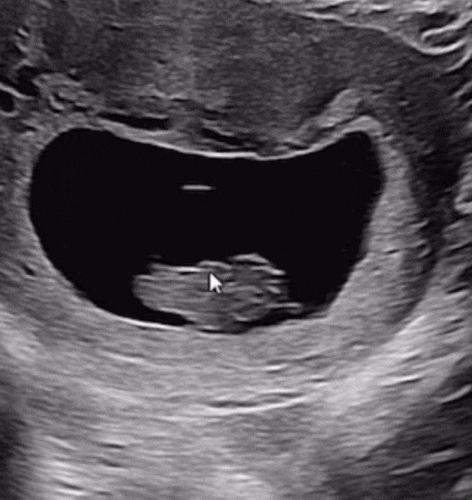

젠또의 기록, 임신7~10주차(젤리곰초음파,임신초기 해외여행,입덧,배크기,태아보험가입)

크지않지만 자그마한 이벤트들로 젠또기록에 헤이해졌었다 글 작성시기는 23주차 ㅎㅎㅎ 중기에 들어섰다 7...

젠또의 기록, 임신6주차(증상, 입덧, 초음파)

올챙이에서 2등신 사람모습으로 ㅎㅎㅎ 점차 자라고있는것같아서 신기하다 입덧이 있다 없다의 반복 ㅠㅠ ...